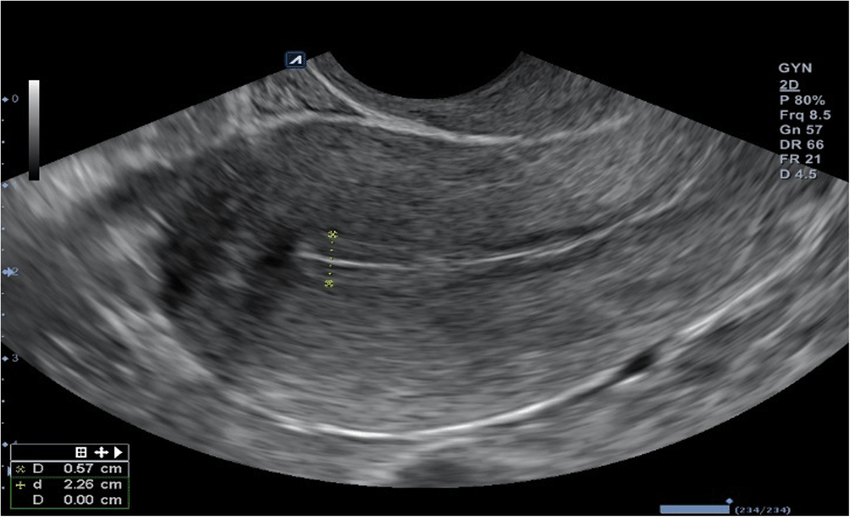

– grootte van de follikels om de eisprong te voorspellen

– Op basis van follikelgrootte kan de meest vruchtbare periode worden bepaald

– Dikte en structuur van het baarmoederslijmvlies (endometrium)

Follikels zijn met vocht gevulde blaasjes waar de eicellen in groeien. Bij een follikelmeting wordt met echo gekeken of en hoe snel de eicellen groeien. De grootte en het aantal follikels geven een indicatie van het optimale moment om een behandeling uit te voeren. Op basis van de follikelmetingen kan de arts het behandelplan aanpassen, bijvoorbeeld door medicatie aan te passen of het juiste tijdstip van inseminatie of punctie vast te stellen.

Bij behandelingen zoals ovulatie-inductie, IUI, IVF en ICSI wordt met vaginale echo’s de groei van follikels (eiblaasjes) gecontroleerd en gekeken naar de dikte van het baarmoederslijmvlies. Dit helpt om het optimale moment voor inseminatie, eicelpunctie of terugplaatsing te bepalen.